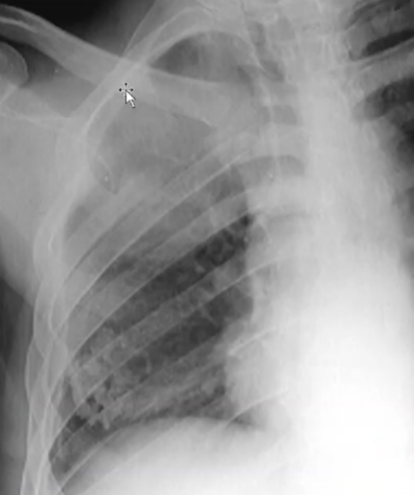

Rx toracică, incidență P-A (centrată pe hemitoracele drept)

DESCRIERE:

în 1/3 sup. a hemitoracelui drept → opacitate de formă triunghiulară, intensitate medie-mare, omogenă

caracter retractil → tracționează traheea și mediastinul de partea afectată + retracția scizurii orizontale (aspect concav)

adenopatii hilare

pahipleurită diafragmatică → îngroșarea pleurei + tracțiuni fibroase

DX: atelectazie prin NBP central endobronșic (pe bronhia lobară sup. dr.)

DD: pneumonie lobară - nu are caracter retractil, prezintă bronhogramă aerică